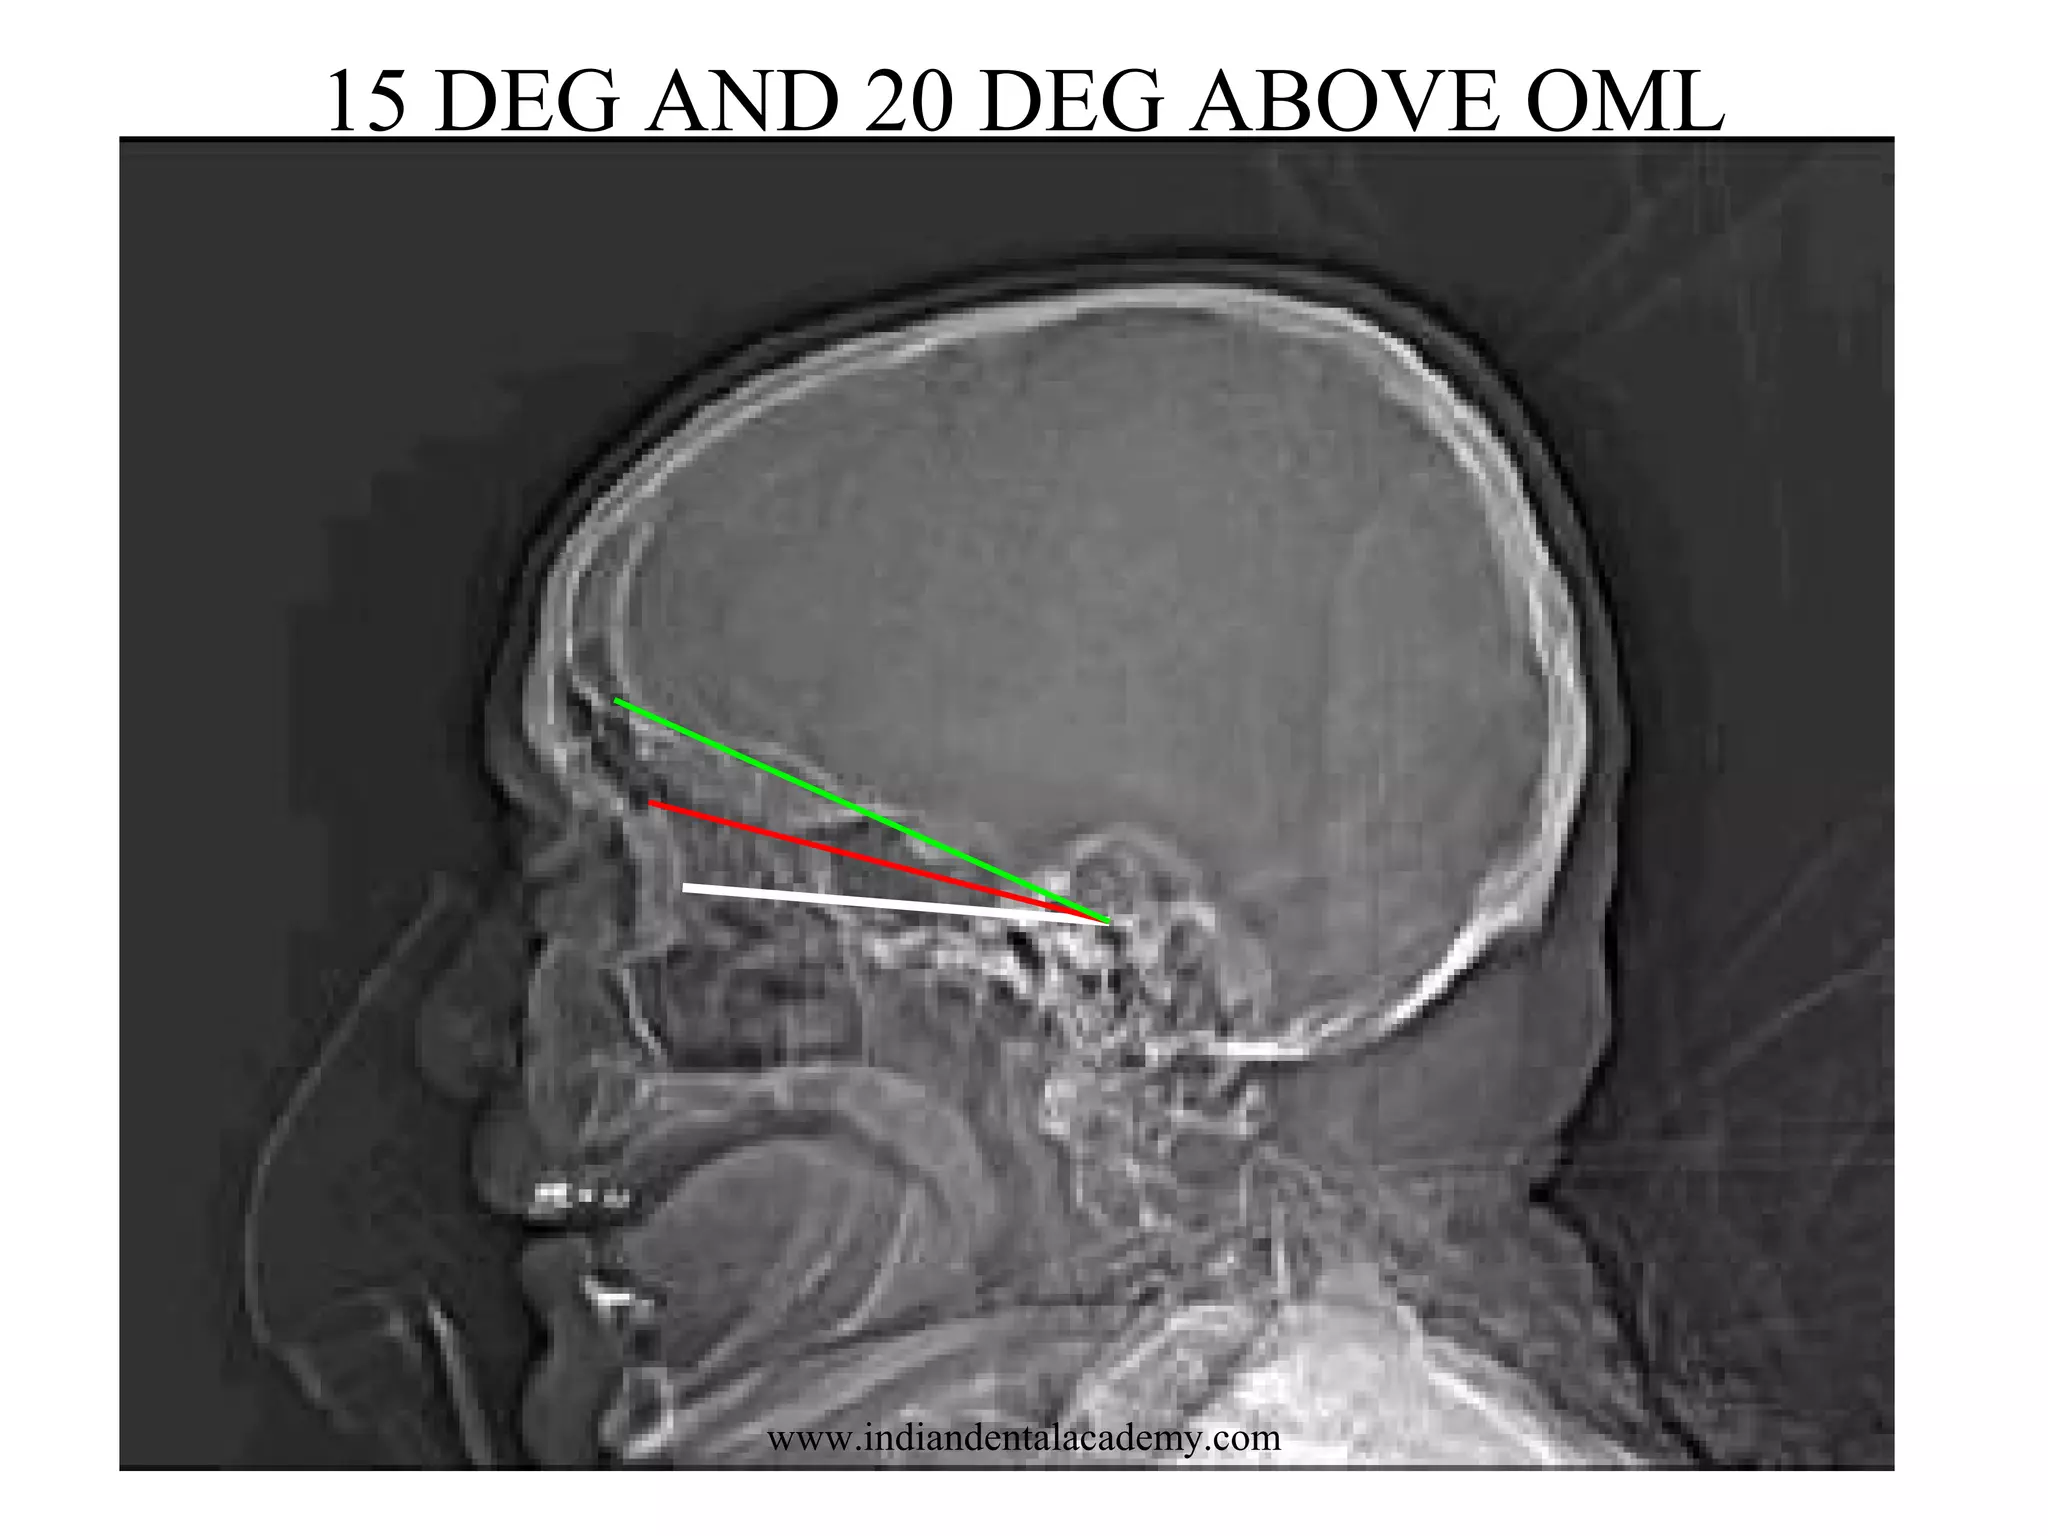

LANDMARK: OML – 15 DEG ABOVE OML

15 DEG AND 20 DEG ABOVE OML

www.indiandentalacademy.com